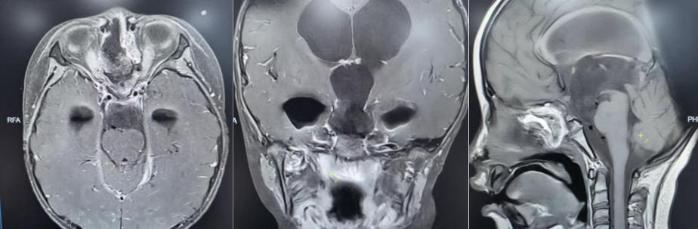

术后垂体MRI增强检查。

手术中,团队借助高清4K神经内镜,细致分离肿瘤与周围神经、血管的粘连。历经3小时,肿瘤被完整切除,下丘脑、垂体柄、视神经等重要结构均得到完好保护。术后病理确诊为颅咽管瘤。

在医护团队的精心照护下,欢欢神经功能障碍明显改善,视力逐渐恢复,头痛症状完全消失,梗阻性脑积水得到有效缓解。之后顺利拔除脑室引流管,未出现脑脊液漏、感染等并发症,内分泌功能也通过药物获得精准调控。